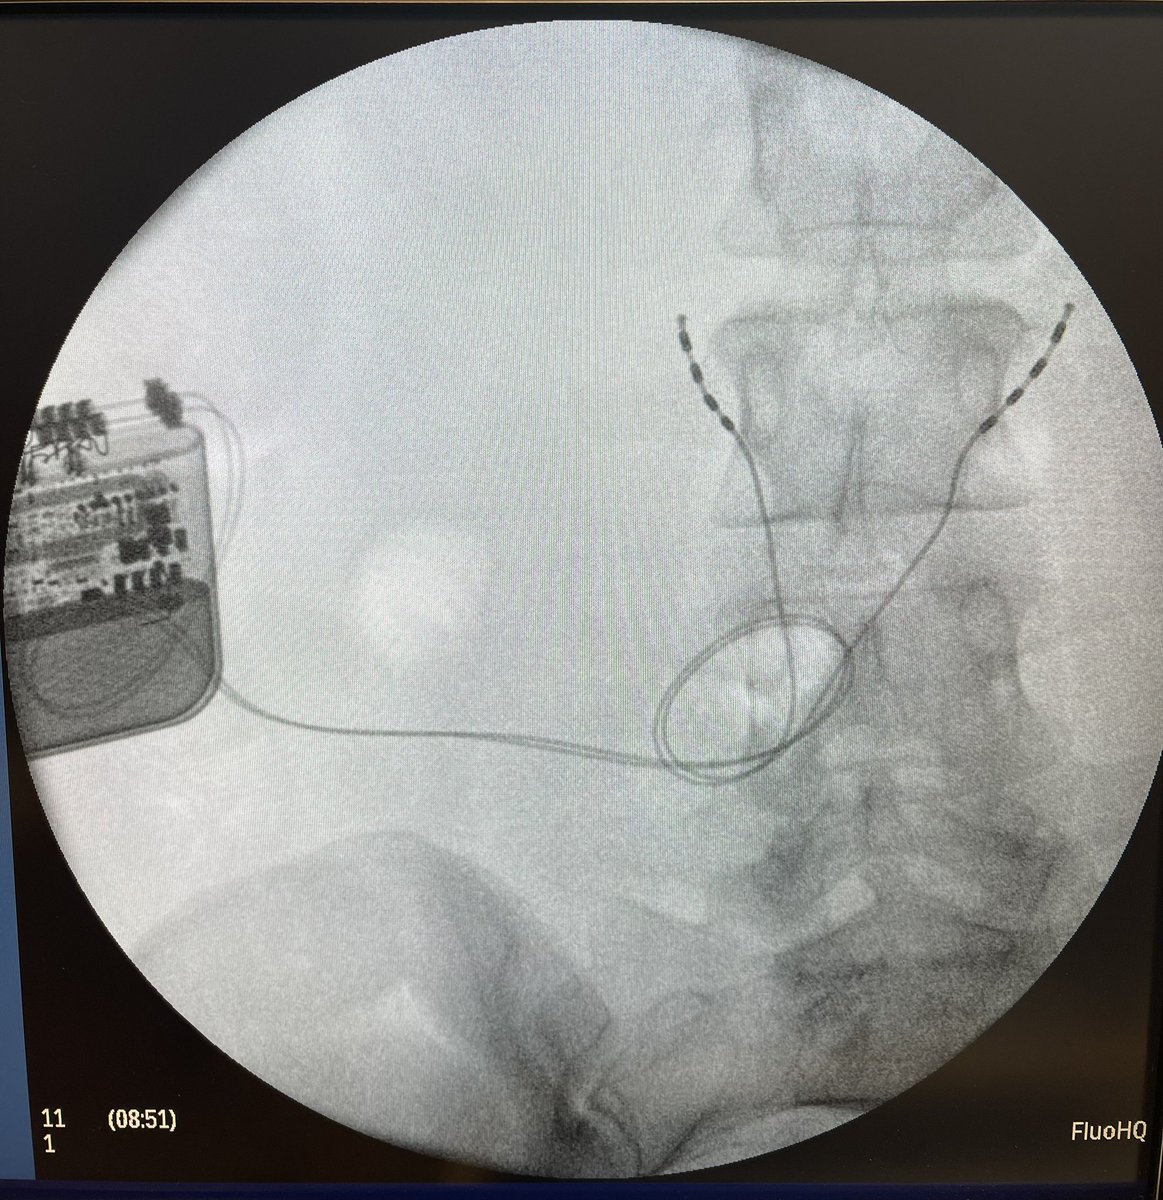

@TheStrykerIVS makes a great product, #SpineJack, that shows up in a lot of cool posts on this and other platforms.

This example was just posted by @neuroradiology - a great example of the genre.